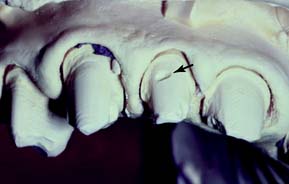

Fig. 6-7 The principles of preparation design for an amalgam foundation restoration differ slightly from those for a conventional extensive amalgam restoration. A, The outline form of a foundation need not include fissures or proximal or occlusal contacts, provided complete caries removal can be accomplished. B, Unsupported enamel (arrow) can sometimes be left when a foundation restoration is prepared. It may facilitate matrix placement and is removed when the crown is prepared. C, Acute cavosurface margins are acceptable for a foundation restoration but not for a definitive amalgam. D, Resistance form is improved by preparing the tooth in a series of steps perpendicular to the direction of occlusal force. E, When pin retention is used, pinholes should be drilled slightly pulpally and at an angle to the root surface (solid line), in comparison with the way they are placed for a conventional extensive amalgam restoration (dashed line). This ensures that retention for the foundation remains after crown preparation.

This can be a particular problem with the extensive reduction necessary for a metal-ceramic restoration. Pin placement is dictated by root furcations and the size of the pulp chamber. In general, pins should be placed further pulpally than when conventional extensive pin amalgams are being provided; to prevent pulp perforation, they should be positioned at a slight angle to the long axis of the tooth. If a pin is slightly exposed during crown preparation, this may not be a problem—in contrast to the conventional pin-amalgam restoration. With a foundation restoration, the pin-amalgam interface receives little stress during function.